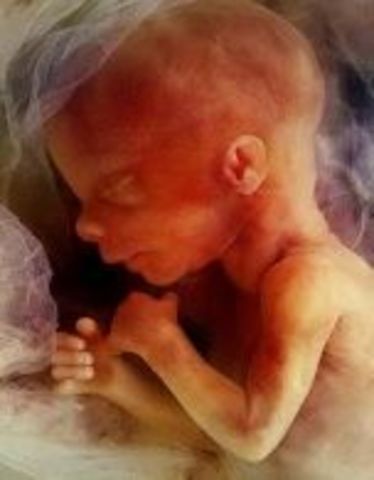

• Week Thirteen: Baby Flexes and Kicks

Week Thirteen: Baby Flexes and Kicks

Ribs are starting to appear and bones are replacing cartilage. The baby is able to open and close their mouth.

• Week Fourteen: Hormones Start Up

Week Fourteen: Hormones Start Up

The baby's facial features start to become more developed. The kidneys start to produce urine.

• Week Fifteen: Bones and Muscles Grow

Week Fifteen: Bones and Muscles Grow

The baby is able to move and make their hand into a fist. Their skin is still pretty thin.